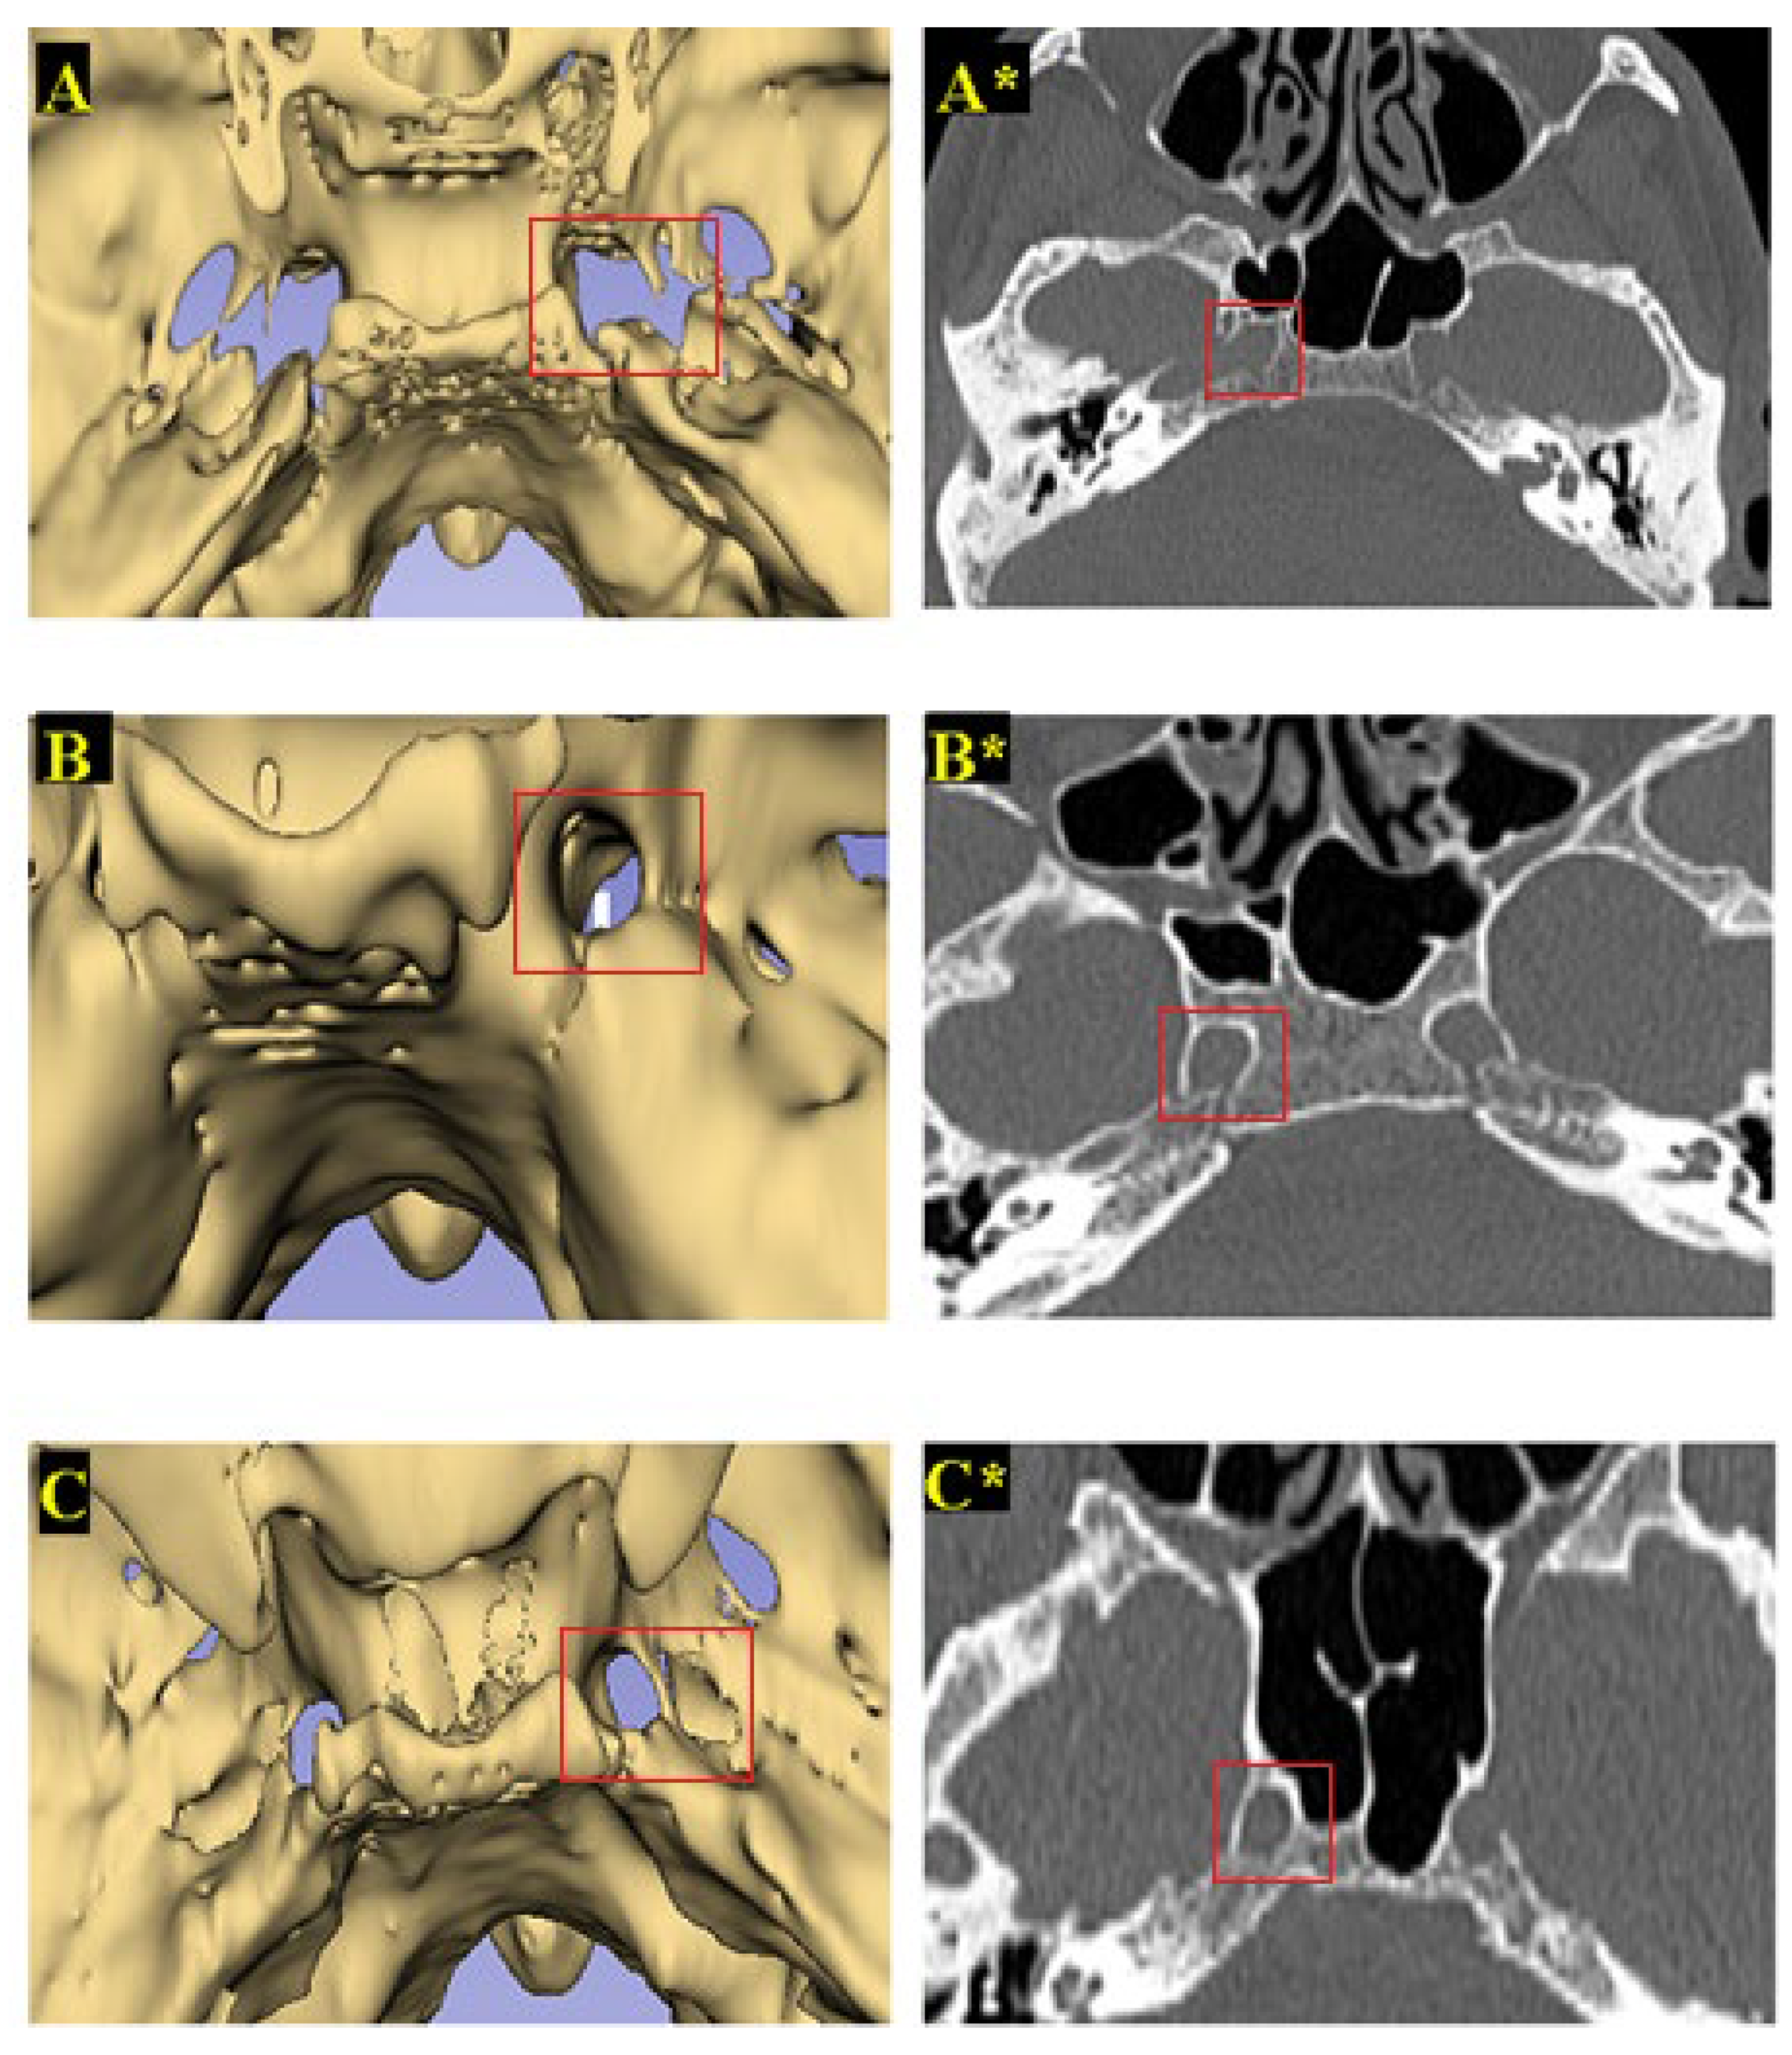

3.2. Classification of FL Types